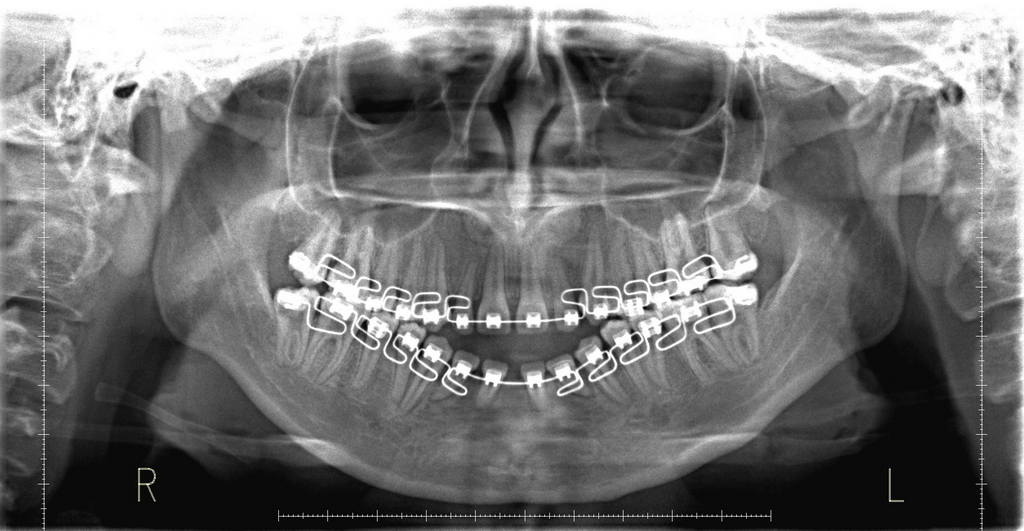

- Radiografía Panorámica

Imagenes de distintos Análisis Radiográficos.